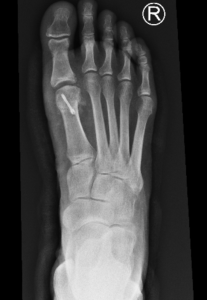

Figure1 and 2: Pre op x-rays showing joint degenerating including joint space narrowing, bone spurs and loose bone fragments.